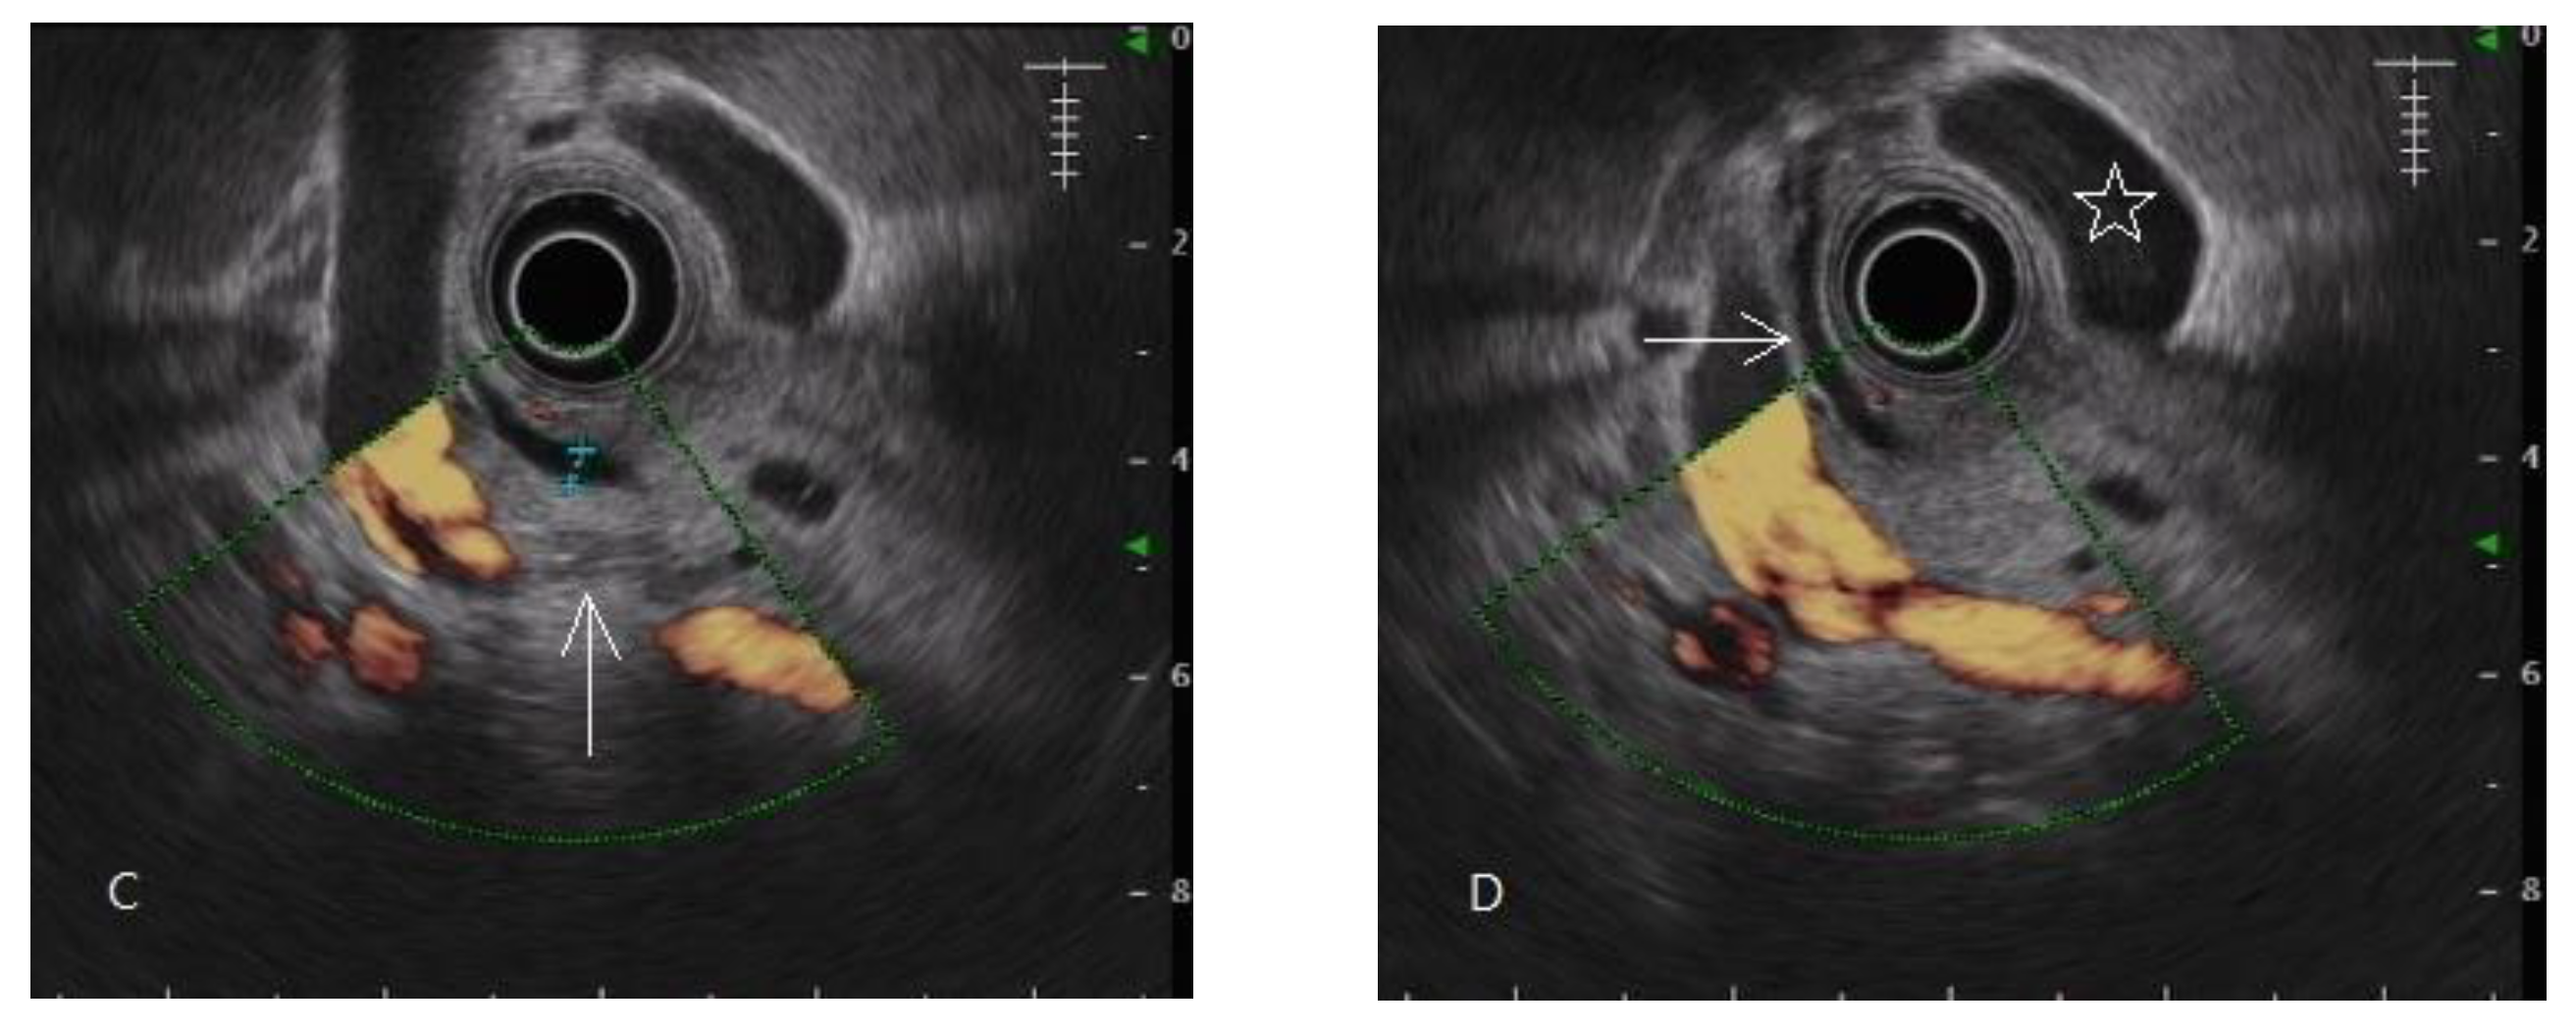

- Domínguez-Muñoz, J.E.; Lariño-Noia, J.; Alvarez-Castro, A.; Nieto, L.; Lojo, S.; Leal, S.; Iglesia-Garcia, D.; Iglesias-Garcia, J. Endoscopic ultrasound-based multimodal evaluation of the pancreas in patients with suspected early chronic pancreatitis. United Eur. Gastroenterol. J. 2020, 8, 790–797. [Google Scholar] [CrossRef]

- Yamashita, Y.; Tanioka, K.; Kawaji, Y.; Tamura, T.; Nuta, J.; Hatamaru, K.; Itonaga, M.; Yoshida, T.; Ida, Y.; Maekita, T.; et al. Utility of Elastography with Endoscopic Ultrasonography Shear-Wave Measurement for Diagnosing Chronic Pancreatitis. Gut Liver 2020, 14, 659–664. [Google Scholar] [CrossRef]